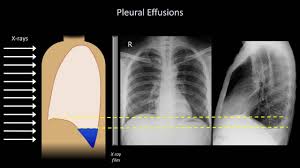

Pleural Effusion Knowledge Amboss

Pleural Effusion Knowledge Amboss from media-us.amboss.com